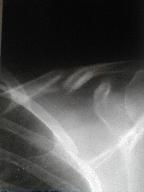

1月8日整復固定後

整復は不充分で骨折端に

軟部組織が挟入している疑いあり

再度整復を試みる |